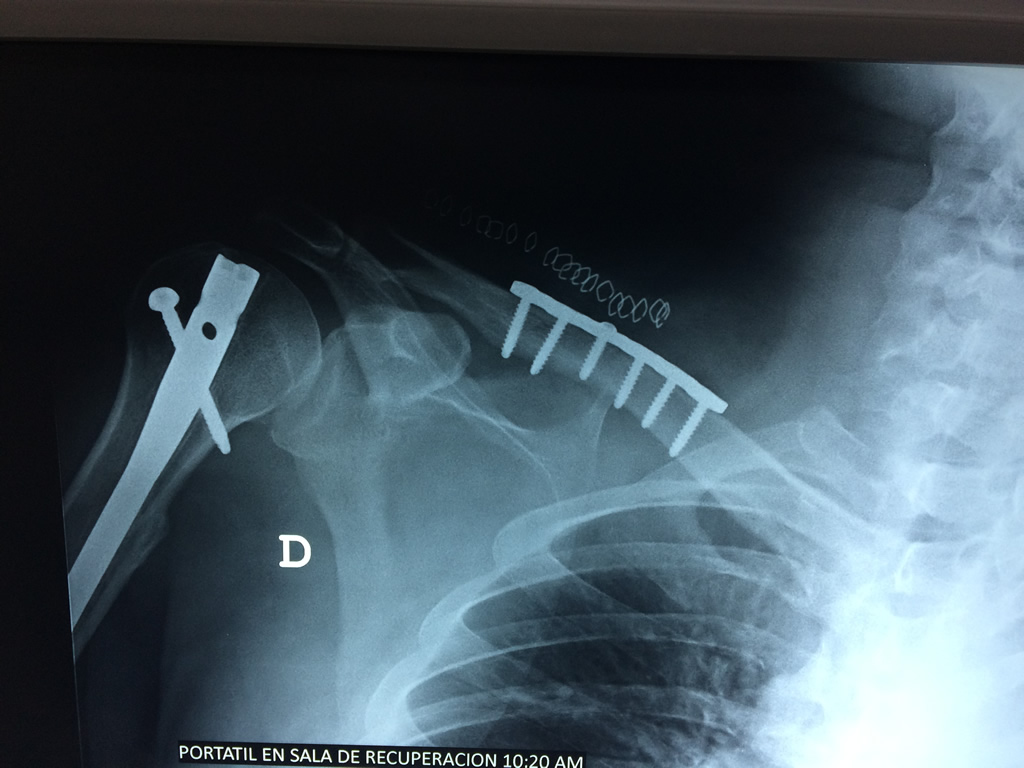

Cirugías de Codos - Clavícula

La clavícula es un hueso largo, con forma de "S" itálica, situado en la parte anterosuperior del tórax. Junto con la escápula forman la cintura escapular. Se puede palpar por toda su longitud y se extiende del esternón al acromion de la escápula, siguiendo una dirección oblicua lateral y posterior.